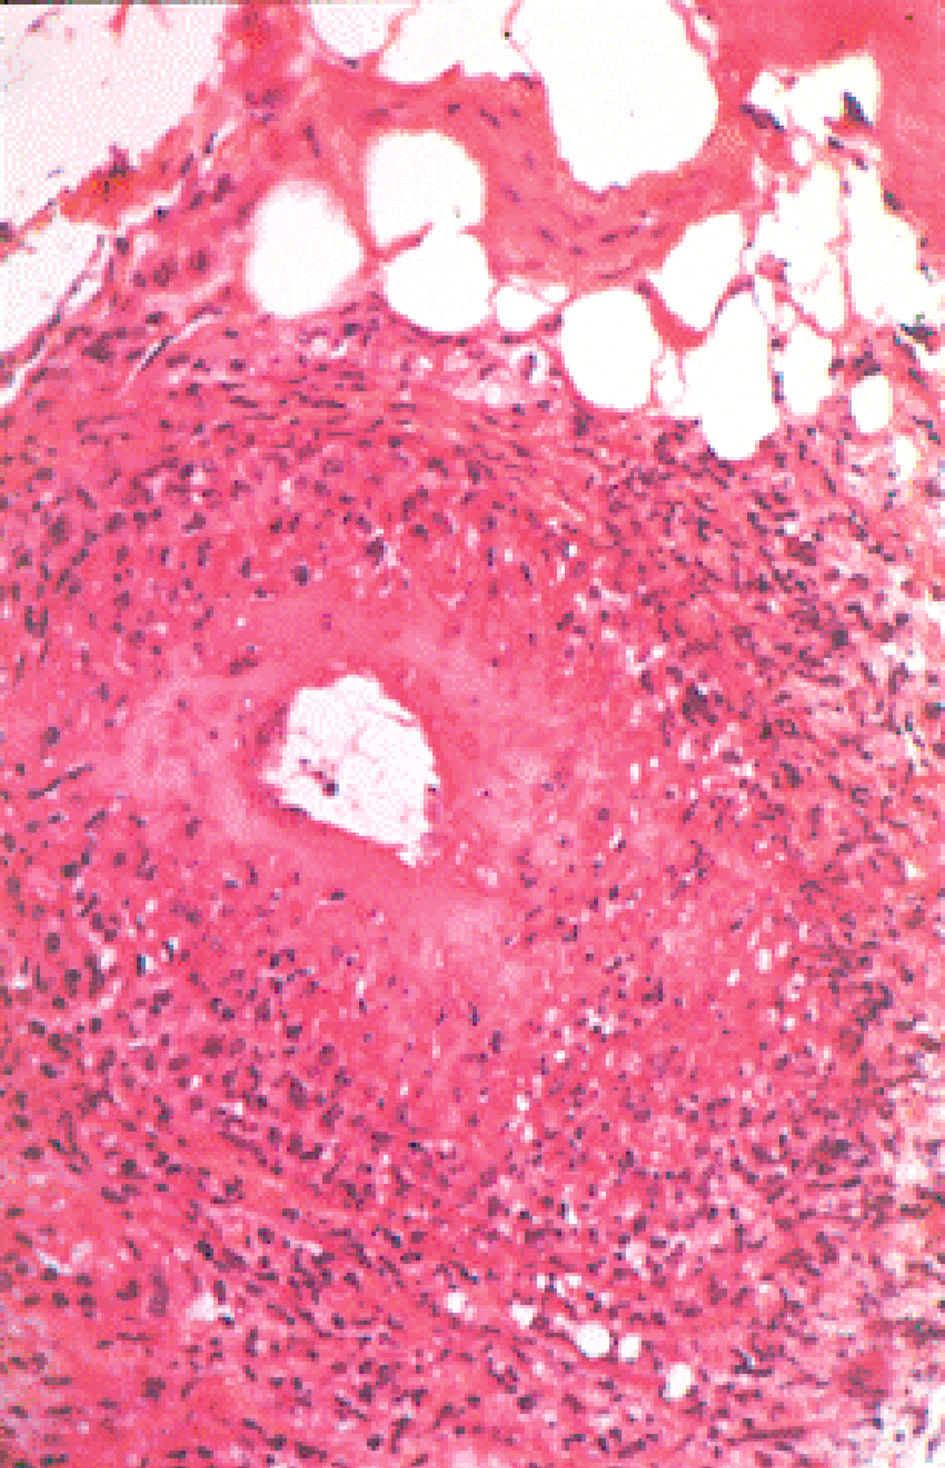

c Biopsie du nerf sensitif

• • La biopsie de nerf sensitif permet dans certains cas difficiles de confirmer le mécanisme de la neuropathie (démyélinisation segmentaire, dégénérescence axonale) et oriente le diagnostic étiologique.

• • Elle conduit à amputer un nerf sensitif. Elle n’est donc jamais pratiquée en première intention.

• • Elle est réalisée le plus souvent sur un nerf sensitif de la jambe (branche sensitive du nerf fibulaire ou nerf sural).

• • Elle permet de mettre en évidence des arguments diagnostiques :

•

• – occlusion artérielle en cas de vascularite et perte axonale fasciculaire;

• – dépôts d’amylose en cas de neuropathie amyloïde;

• – lésions inflammatoires et démyélinisation/remyélinisation d’une polyneuropathie inflammatoire démyélinisante chronique.